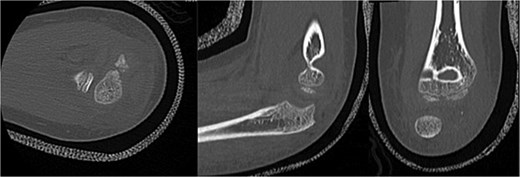

Initial radiographs following closed reduction and casting demonstrated fractures of the proximal ulna and radial neck, with improved alignment but limited bony detail (Fig. 1a and b). Elbow effusion was also noted. A CT scan performed 3 days later showed 18° apex-medial angulation of the radial neck fracture, slight inferior subluxation of the radial head, and linear calcification near the ulnotrochlear interval, concerning for an intra-articular fragment (Fig. 2).

CT scan demonstrating radial neck angulation, radiocapitellar subluxation, and linear calcification near the trochlear notch.